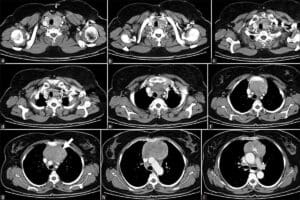

Turkish centers provide a full spectrum of neuroradiology services, from high‑resolution MRI and CT scans to image‑guided minimally invasive interventions such as endovascular coiling or stereotactic radiosurgery. Multidisciplinary teams—radiologists, neurologists,... d interventional specialists—collaborate to design individualized care plans tailored to each diagnosis. Many hospitals also offer advanced post‑procedure monitoring and rehabilitation services within the same campus, ensuring continuity of care without the need for multiple referrals. By focusing on state‑of‑the‑art equipment and a patient‑centered approach, Turkey’s providers aim to deliver outcomes comparable to those found in top European institutions.